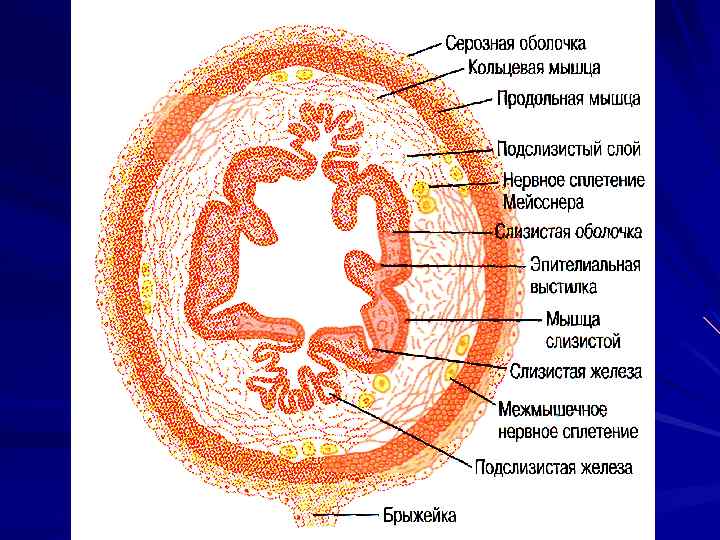

Стенка ПВТ

Стенка ПВТ

МЫШЕЧНЫЕ СЛОИ СЧИТАЯ СНАРУЖИ: 1. ПРОДОЛЬНЫЕ 2. ЦИРКУЛЯРНЫЕ (КОЛЬЦЕВЫЕ) 3. КОСЫЕ (ТОЛЬКО В ЖЕЛУДКЕ)

МЫШЕЧНЫЕ СЛОИ СЧИТАЯ СНАРУЖИ: 1. ПРОДОЛЬНЫЕ 2. ЦИРКУЛЯРНЫЕ (КОЛЬЦЕВЫЕ) 3. КОСЫЕ (ТОЛЬКО В ЖЕЛУДКЕ)